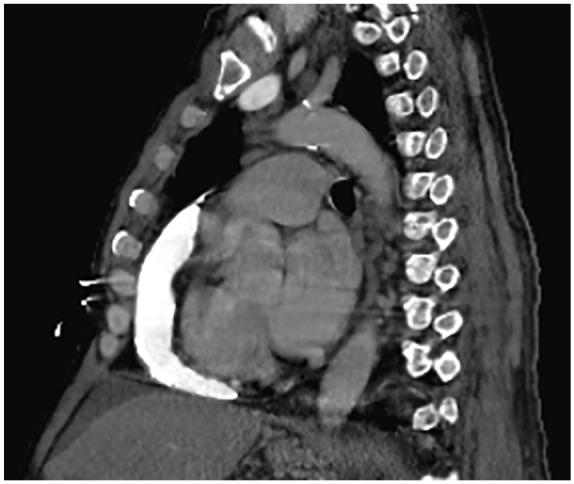

Although well documented, constrictive pericarditis is a rare entity and an uncommon cause of heart failure. A stiff and noncompliant pericardium creates the disease's unique hemodynamics and leads to elevated venous pressures, hepatic sinusoidal congestion, and draining of protein-rich fluid into the peritoneal cavity presenting as ascites. The low incidence in addition to its varied and subtle clinical presentations can often lead to a delay in diagnosis. Here, we present 2 clinical cases of constrictive pericarditis in which ascitic fluid analysis was important-one patient who presented with new-onset ascites with concern for cirrhosis and another patient who presented with symptoms concerning for heart failure with ascites. Through their hospital course and workup, we highlight the importance of diagnostic sampling of ascitic fluid to prompt the consideration of constrictive pericarditis followed by utilizing advanced diagnostics, such as echocardiogram and cardiac catheterization to reach the correct diagnosis in an otherwise often overlooked pathology.

尽管已有充分的文献记载,但缩窄性心包炎是一种罕见的疾病,也是心力衰竭不太常见的病因。坚硬且缺乏顺应性的心包会导致该病独特的血液动力学变化,进而导致静脉压升高、肝窦充血,并使富含蛋白质的液体引流到腹腔,表现为腹水。其发病率低,加之临床表现多样且不明显,往往会导致诊断延迟。在此,我们介绍了 2 例缩窄性心包炎的临床病例,其中腹水分析很重要——1 例患者因新出现的腹水就诊,病因考虑为肝硬化,另 1 例患者因疑似心力衰竭合并腹水就诊。通过他们的住院过程和检查,我们强调了诊断性腹水取样的重要性,以促使考虑缩窄性心包炎,然后利用超声心动图和心导管等先进诊断方法来明确诊断,否则这种疾病往往会被忽视。